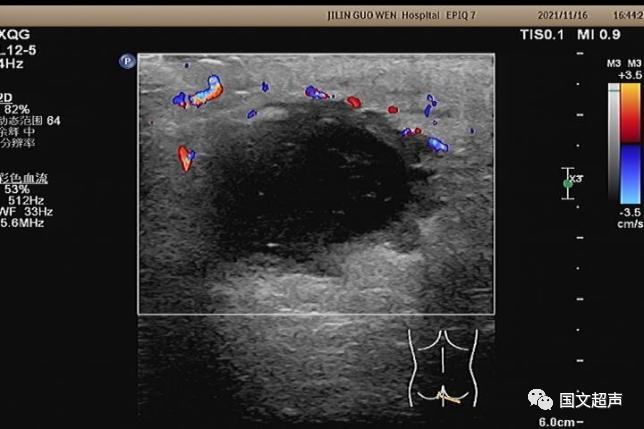

超聲檢查所見:

肛周:7點(diǎn)鐘方向皮下脂肪層內(nèi)探及不均質(zhì)低無回聲包塊,范圍約4.6*3.0cm,較淺處距體表約0.6cm,邊界不清,周圍軟組織回聲增強(qiáng),CDFI:周邊血流信號豐富,輕加壓探頭有涌動(dòng)感,如下圖: